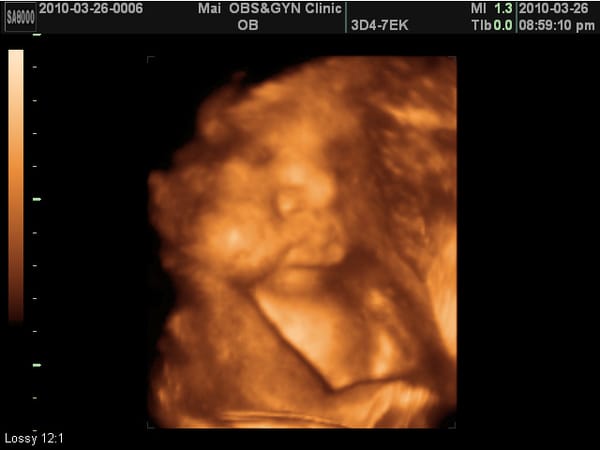

這次又看得到4D照了,相當有肉,臉頰有肉、鼻子有肉、嘴巴也很有肉、連胸部也擠出一團肉~~~

我一直說可能是因為頭在下被擠壓的關係,所以看起來很有肉啦~不過M醫生卻沒有回我話。

肚子快要爆炸了,37w紀念一拍。